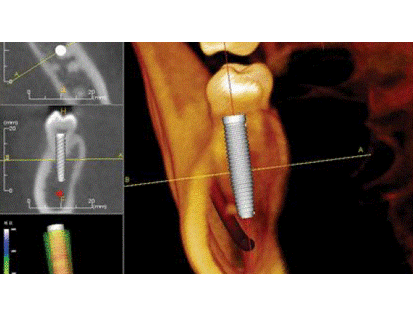

Procédures implantaires dentaires virtuelles

AUGUSTA, GA, États-Unis: Le Virtual Dental Implant Simulation Program, programme de simulation pour formation, un jeu d'ordinateur réaliste ...